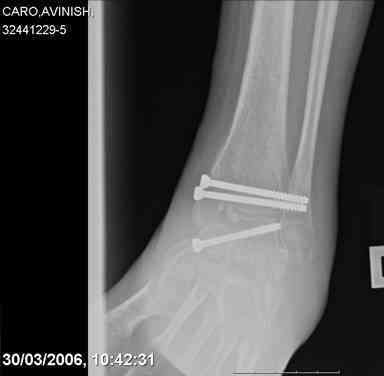

ya by popytalsya sobrat talus anatomichno,seichas pozdno operirovat

iz za oteka,po etomy distrakziya apparatom budet optmalna.Posyalu vam

podobyai moi sluchai.